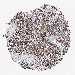

BRCA TCGA BRCA VALIDATION PROTEIN EXPRESSION